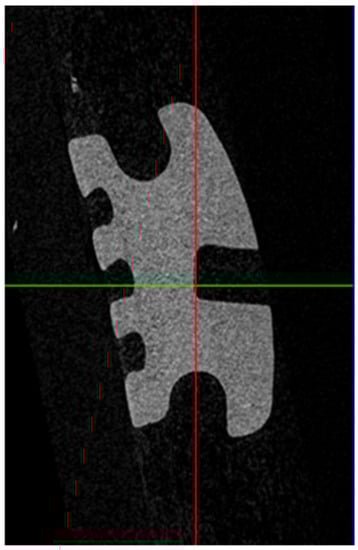

2. Materials and Methods